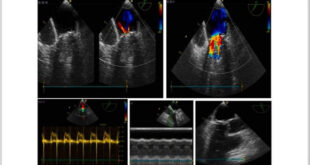

المزيدفي مشفى الباسل لأمراض وجراحة القلب بدمشق… فريق طبي ينجح في علاج حالة نادرة لـ “أم الدم الكاذبة”

دمشق-سانا نجح فريق طبي في الهيئة العامة لمشفى الشهيد باسل الأسد لأمراض